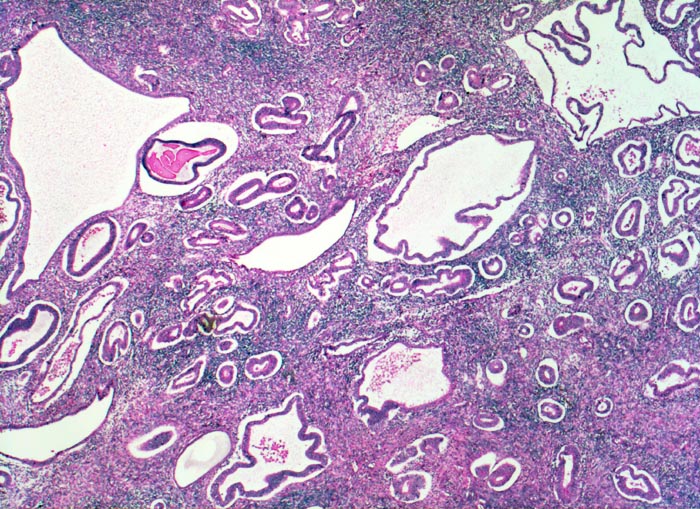

glandulär zystische Hyperplasie der Korpusmukosa

Hoch aufgebaute Mukosa mit unregelmässig zystisch dilatierten Drüsen (sogenanntes Schweizerkäsemuster). Zwischen den einzelnen Drüsen liegt reichlich Stroma.

Die Endometriumhyperplasie wird eingeteilt in eine einfache Hyperplasie mit oder ohne Atypie (meist ohne Atypie) oder eine komplexe Hyperplasie mit oder ohne Atypie. Die vorliegende einfache Hyperplasie entwickelt sich nur selten zu einem Endometriumkarzinom weiter.